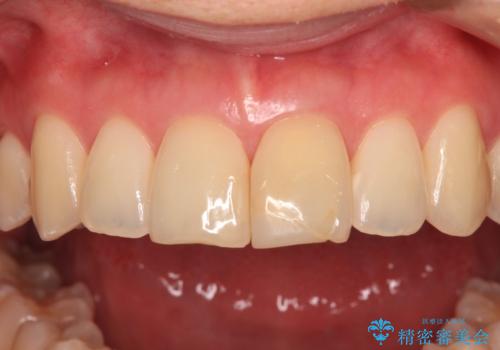

変色した前歯 オールセラミッククラウンにより審美歯科治療

- 神経を取り除いたことで経年変色した前歯2本を気にして来院された患者様です。

根管治療を行う必要はないと判断し、双方の歯にグラスファイバーを含有した土台を植立してオールセラミッククラウンにて補綴することとしました。

色調が周囲の歯とアウトともに、表面のつぎはぎや穴を封鎖した際の段差などが解消され、天然歯のような感触となりました。